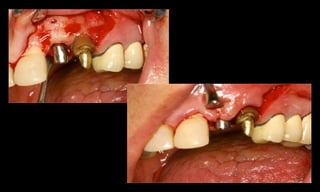

10-10-2005

Novembro de 2005

24-01-2006

Cone Morse